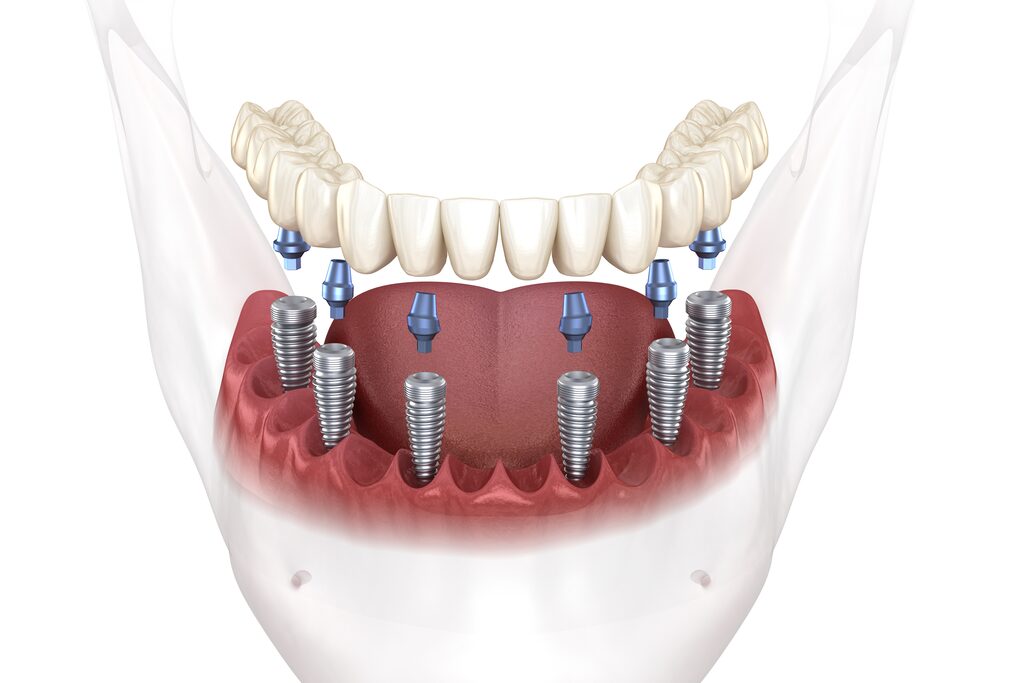

Implantate sind künstliche Zahnwurzeln, die in den Knochen fest verankert werden. Nach einer Einheilphase von zwei bis sechs Monaten bildet sich ein fester Verbund aus Implantat und Knochen, so dass eine stabile Trägereinheit entsteht. Anschließend wird ein individuell gefertigter Zahnersatz auf den Implantaten befestigt. Zahnimplantate können bei einzelnen Lücken als auch bei völliger Zahnlosigkeit eingesetzt werden.

Das Implantat besteht aus reinem Titan, einem Metall mit hoher Verträglichkeit und Stabilität. Das Reintitan löst keine Fremdkörperabstoßung oder allergische Reaktion aus. Alternativ können auch Keramikimplantate gesetzt werden.

Implantate zeichnen sich durch ihre hohe Ästhetik und Stabilität aus. Sie sitzen fest im Knochen und werden daher vom Patienten wie ein echter Zahn wahrgenommen. Einen weiteren Vorteil stellt die gute Pflegbarkeit dar. Im Gegensatz zu einer Brückenversorgung kann zwischen Implantat und Nachbarzahn leicht gereinigt werden. Bei einer Einzelzahnlücke bleiben die gesunden Nachbarzähne ebenfalls völlig unberührt, was bei einer Brücke nicht möglich ist. Im Gegensatz zu Prothesen baut sich der Kieferknochen nach Zahnverlust nicht ab, da die Kaukräfte günstiger auf den Knochen wirken, wenn Implantate vorhanden sind. Bei guter Pflege und regelmäßiger professioneller Zahnreinigung zeichnen sich Implantate durch eine hohe Langlebigkeit aus. Der Zahnersatz durch Implantate geht mit einem hohen Kaukomfort und somit mit einem gesteigerten Lebensgefühl einher.